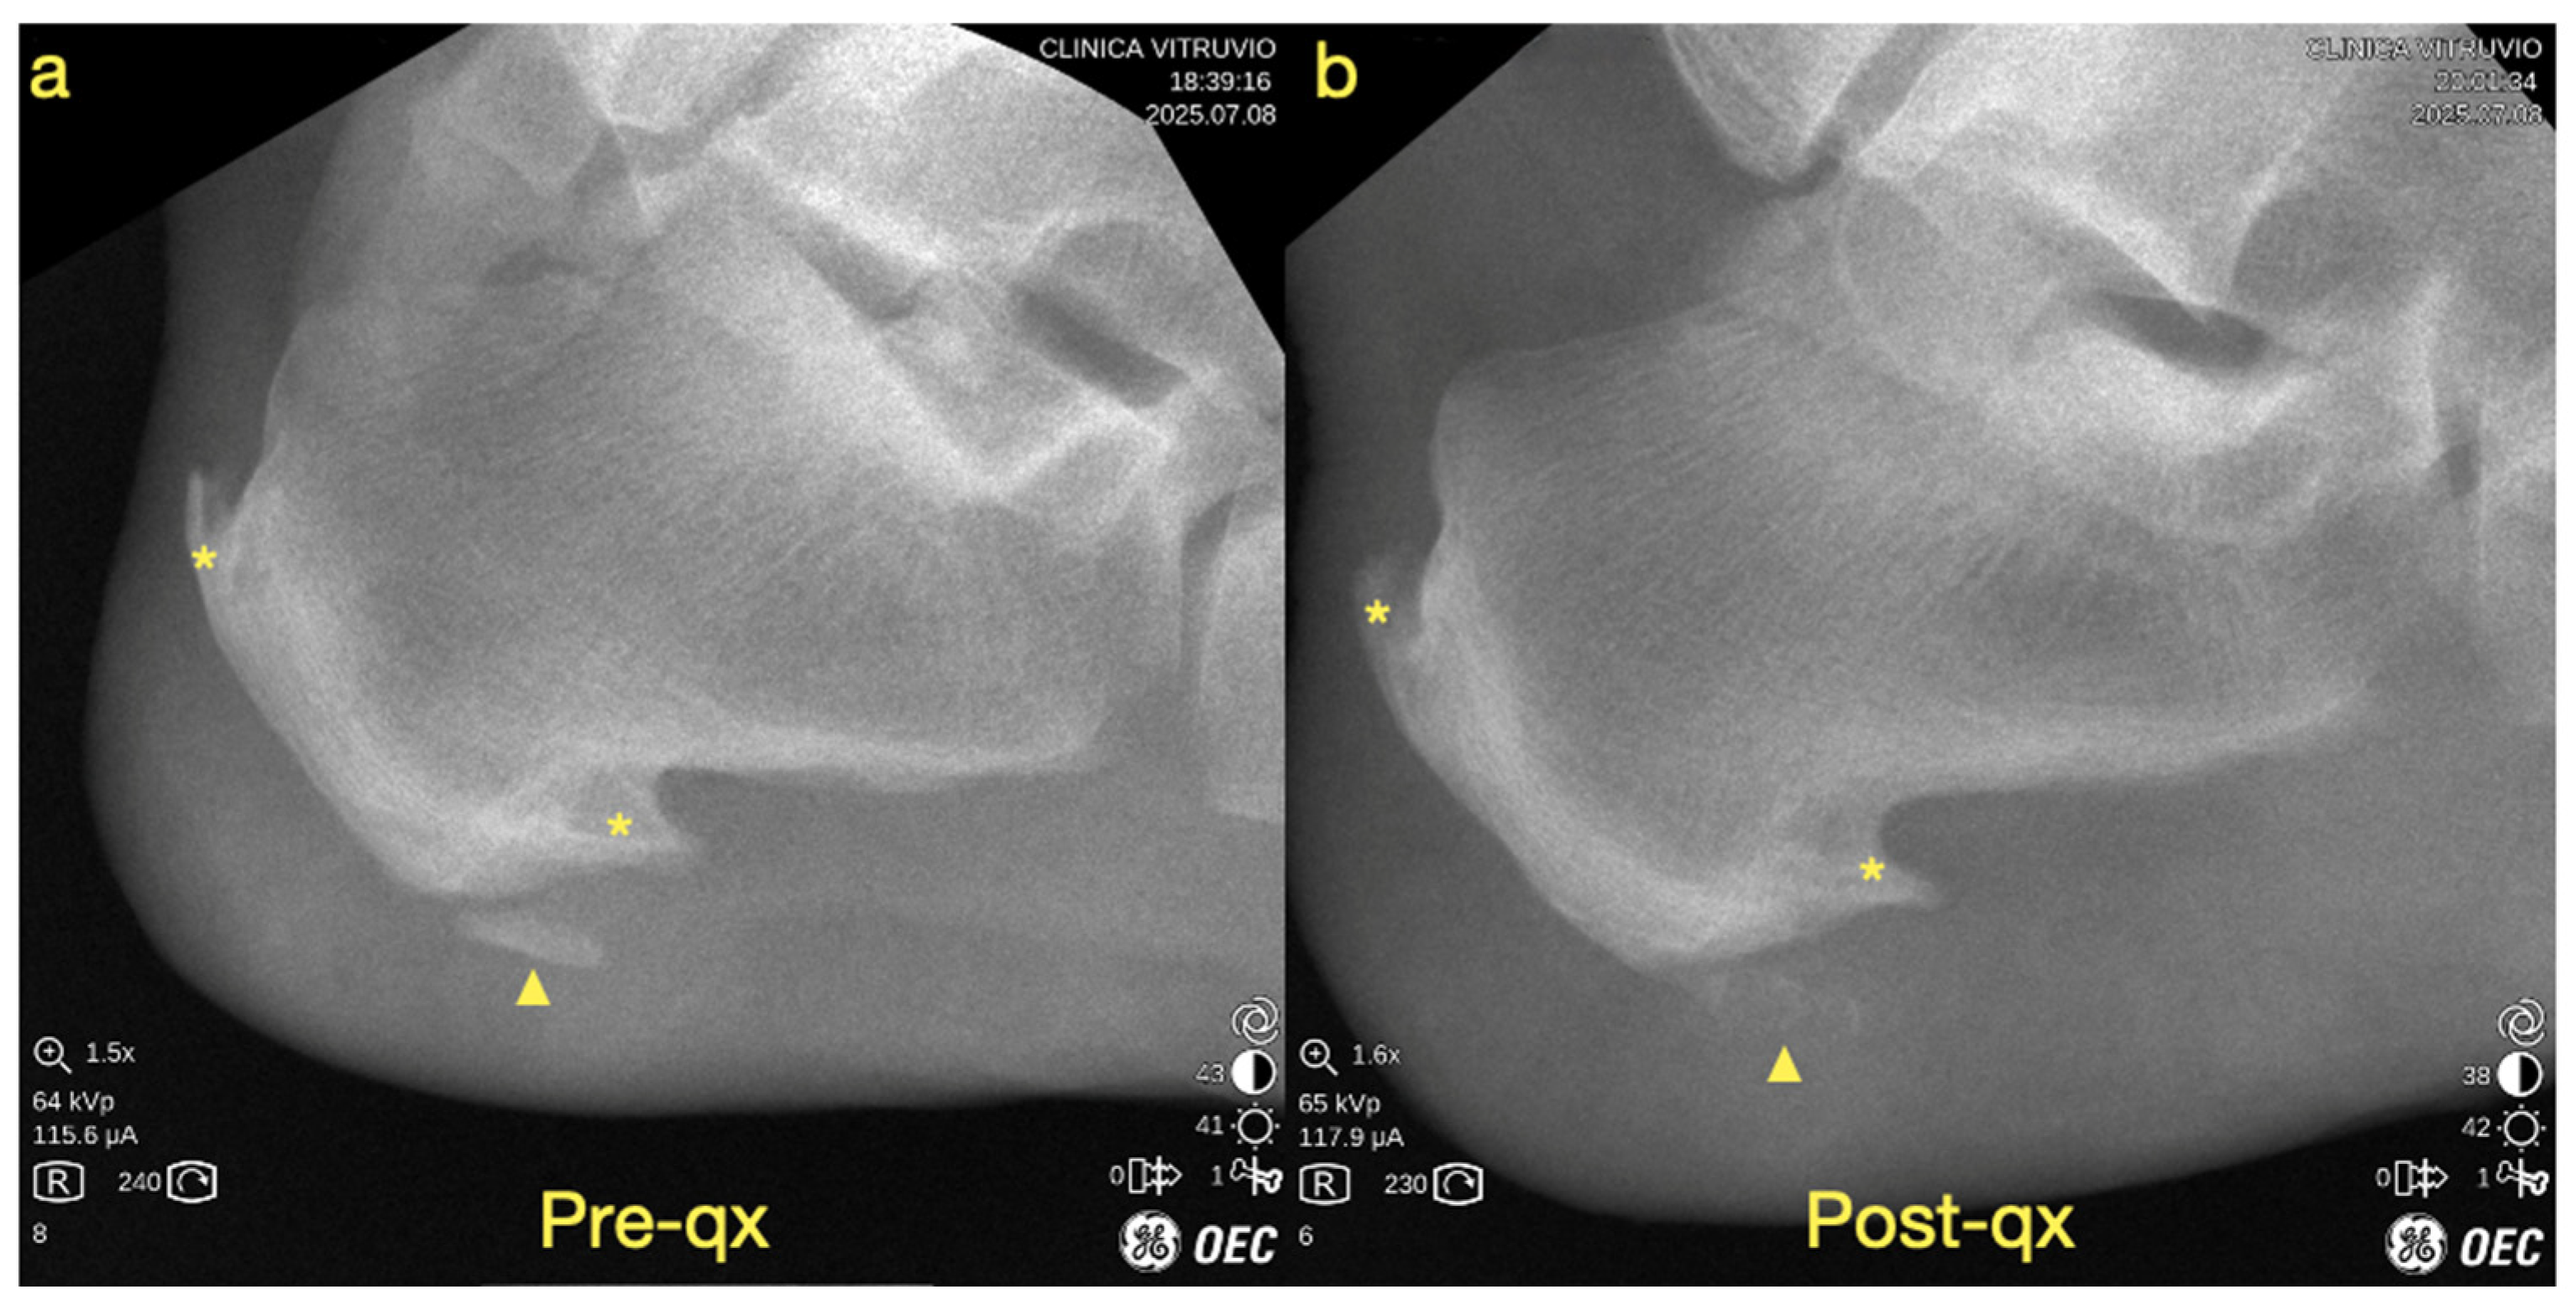

We report the case of an 82-year-old male patient. He has a medical history of high blood pressure and high uric acid levels, and he previously underwent a prostatectomy. The patient experienced plantar heel pain for two years, which became worse with weight-bearing activities. The pain was not linked with post-static dyskinesia and intensified when walking barefoot or on hard surfaces. He described the sensation as feeling like “walking on a stone.” For diagnostic purposes, plain radiographs and magnetic resonance imaging (MRI) were performed in order to establish a differential diagnosis and to confirm the presence of heterotopic ossification at the plantar fascia (Figure 1). The diagnosis of heterotopic ossification was established upon identifying a bone formation with visible trabeculae within the substance of the plantar fascia and a clear separation from the bony insertion, allowing differentiation from a calcaneal spur or enthesophyte.

Figure 1. (a) Plain radiograph, (b) fluoroscopic image, (c) MRI scan, (d) longitudinal (long-axis) ultrasound of the plantar fascia, and (e) transverse (short-axis) ultrasound of the plantar fascia. The yellow asterisk indicates the plantar enthesophyte (heel spur), the yellow arrowhead denotes the intrafascial heterotopic ossification, the white arrows outline the plantar fascia, and the red asterisk highlights the lesion involving the macrocameras of the plantar fat pad.